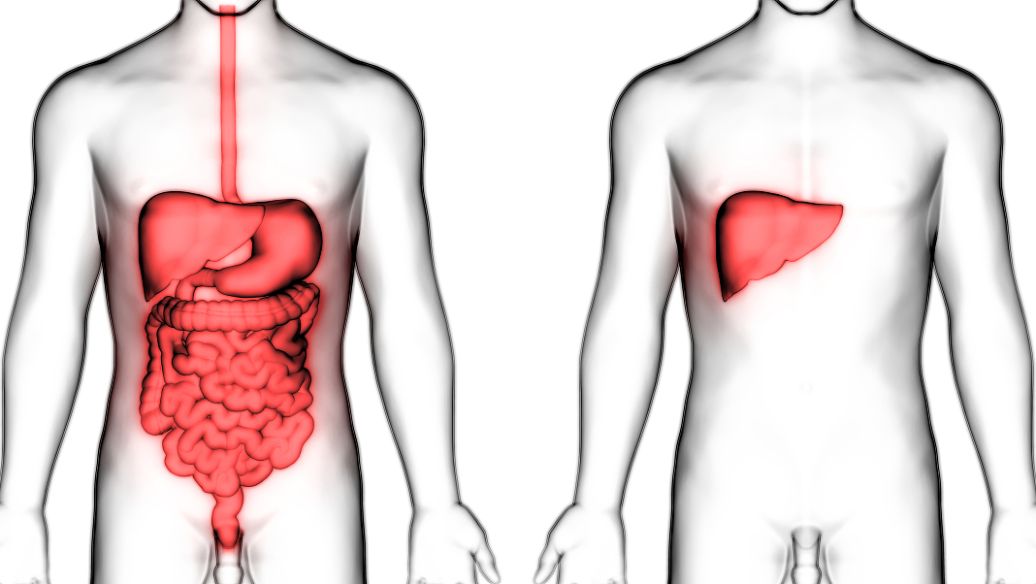

许多朋友在生活中可能会发现自己的白眼球会有充血的情况,一般出现这样的情况,因素是有很多的。睡眠不足,长时间使用眼睛,一些眼科疾病等等都有可能会导致这样的情况出现。

5.可能是球结膜下出血,球结膜下出血大都因高血压动脉硬化,凝血功能不良及局部血管炎症或脆性增加,用力屏气或外伤所致。